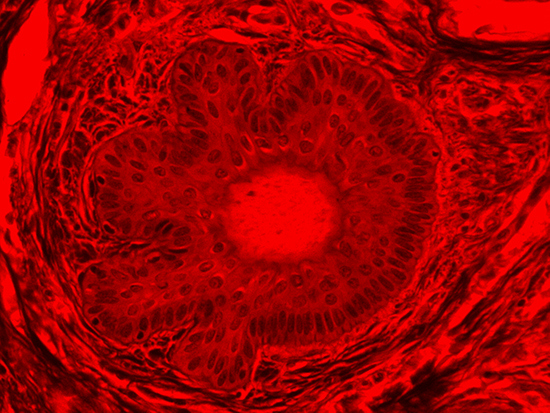

Figure 1: Brightfield Image of Dermal Tissue

When comparing Figures 1 and 2, the visual differences are significant. A brightfield image is formed with the illumination source below the sample, and then transmitted light propagates through the sample to the sensor forming a bright, white background with sharp color. A darkfield image is formed by directing light at an oblique angle through the sample, forming a hollow cone of light which is collected by the objective. Darkfield illumination typically yields a dark background with sharp color, but in the case of Figure 2, the collagen and muscle fibers interfered with the light path and caused a blur of light and color. The dark background is hardly evident and only two distinct colors are visible. When analyzing histological stains, brightfield illumination is the preferred technique for lighting a sample.